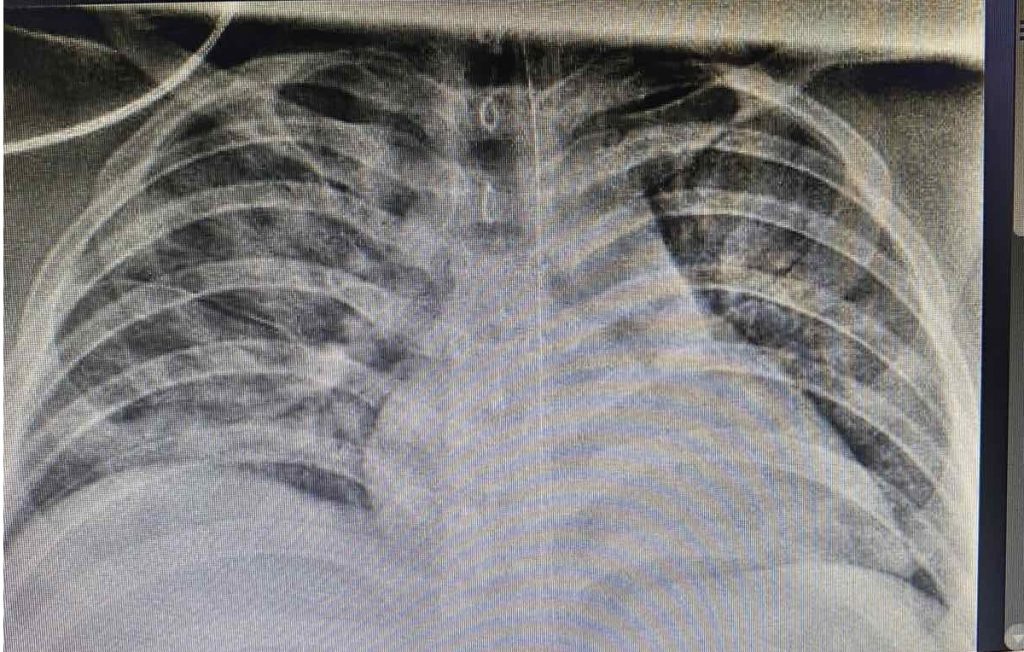

| X-quang ngực của bệnh nhi cho thấy, hình ảnh tổn thương thâm nhiễm phổi nặng lan tỏa 2 phế trường. Ảnh: BSCC. |

Tuy nhiên, tình trạng của bệnh nhi diễn tiến xấu hơn. Lúc đầu, SpO2 của bệnh nhi nâng lên 92-93%, sau đó giảm còn 84-86%. Các bác sĩ đã cho bệnh nhi thở máy không xâm nhập, nhưng vẫn không cải thiện. Hình ảnh X-quang phổi cho thấy tổn thương phổi nặng lan tỏa 2 bên, biểu hiện hội chứng suy hô hấp cấp tiến triển (ARDS), được đặt nội khí quản thở máy.